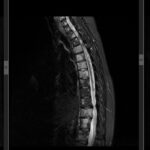

Investigațiile imagistice reprezintă o componentă importantă în diagnosticarea sindromului cozii de cal.

Imagistica prin rezonanță magnetică (RMN) este considerată metoda de referință (interpretare rmn), permițând vizualizarea precisă a structurilor coloanei vertebrale și a compresiunii asupra rădăcinilor nervoase ale cozii de cal.

RMN-ul poate identifica cauzele subiacente, cum ar fi hernia de disc lombară, tumori sau stenoza spinală.